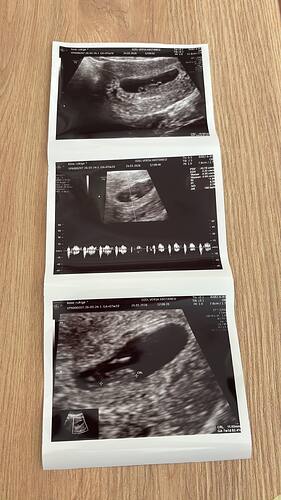

Hep ben tahmin yapıyordum kızlar şimdi ben sizden tahmin bekliyorum Bizim cinsiyetimiz ne teyzeler yorumlarınızı bekliyorum…

Allah nasip ederse inşallah 4. gebeliğim canım